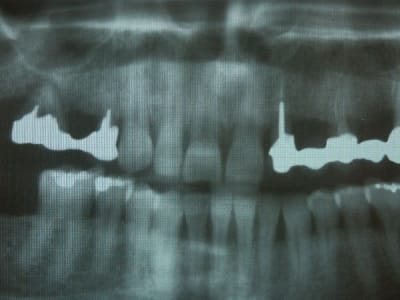

pour relancer le débat, dans un cas comme ça vous faites quoi?

la radio...